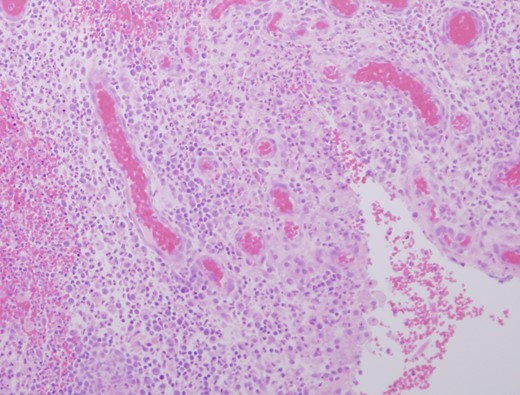

The patient re-presented 5 months later with two further episodes of breast sepsis at the same site which failed to settle with conservative treatment. After discussion, total duct excision was carried out in an attempt to resolve the chronic sepsis. Histological examination showed benign breast tissue with evidence of acute and chronic inflammation in association with micro-abscess formation (Fig. 1). Further sections showed hair shaft material within a duct and associated active chronic inflammation (Fig. 2), demonstrating the pilonidal nature of the breast sepsis. Subsequent discussion with the surgeon revealed the patient to be a hairdresser. Review of the first set of biopsies identified some possible hair shaft material, but this was not conclusive. On post-operative review the patient is well with no further episodes of sepsis.

Granulation tissue and micro abscess formation in total duct excision specimen (HE ×200).